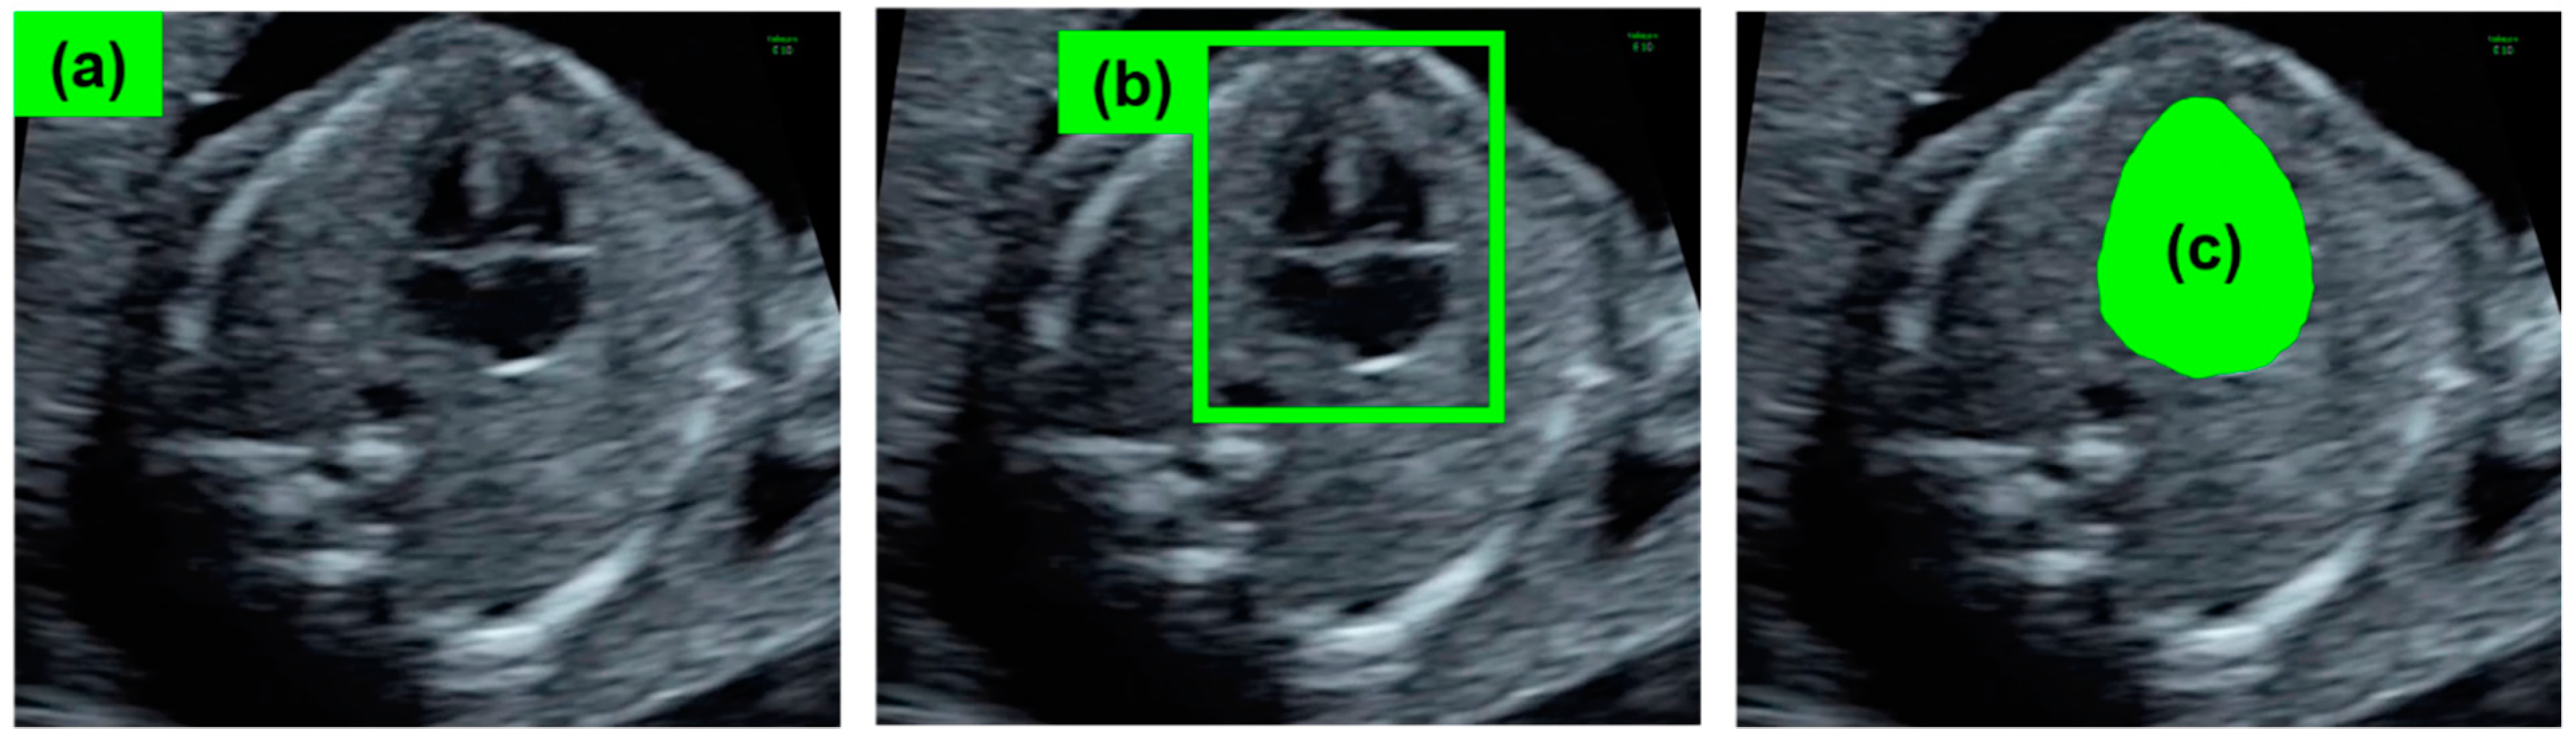

- Dozen, A.; Komatsu, M.; Sakai, A.; Komatsu, R.; Shozu, K.; Machino, H.; Yasutomi, S.; Arakaki, T.; Asada, K.; Kaneko, S. Image Segmentation of the Ventricular Septum in Fetal Cardiac Ultrasound Videos Based on Deep Learning Using Time-Series Information. Biomolecules 2020, 10, 1526. [Google Scholar] [CrossRef]

- Komatsu, M.; Sakai, A.; Komatsu, R.; Matsuoka, R.; Yasutomi, S.; Shozu, K.; Dozen, A.; Machino, H.; Hidaka, H.; Arakaki, T.; et al. Detection of Cardiac Structural Abnormalities in Fetal Ultrasound Videos Using Deep Learning. Appl. Sci. 2021, 11, 371. [Google Scholar] [CrossRef]